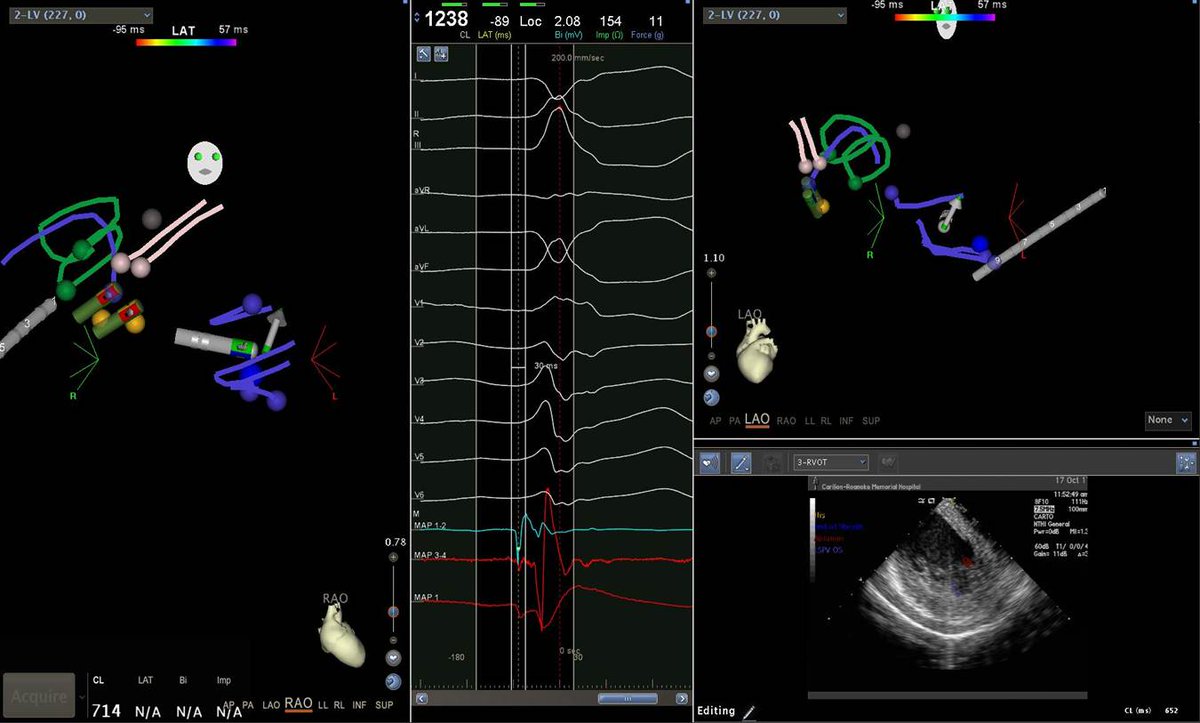

65 yo with symptomatic multifocal PVCs, ~30K, EF 45%,  3 different PVCs were ablated today..fun & require patience, thanks to the team!